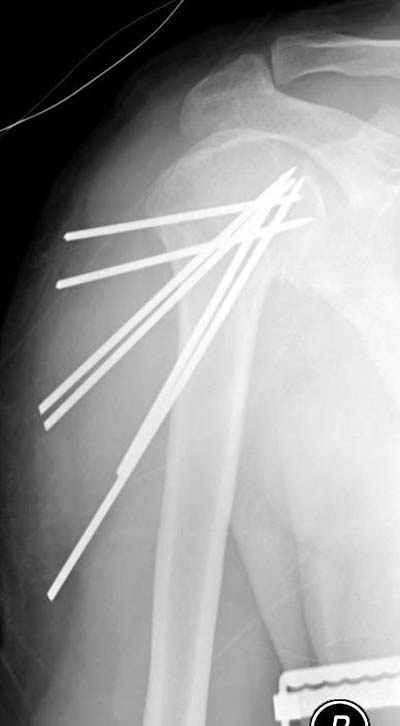

Здесь случай перелома-вывиха плеча, больному 56 лет, после "дважды" закрытой неудачной репозиции, опять же ургентно взяли в операционную, после полного общего обезболивания попытались сделать репозицию, и фиксацию провели спицами.

Больной находился в повязке, примерно напоминяющей косыночную, рекомендованы движения в локтевом суставе и маятниковые движения в плече, спицы удалены в три недели (были случаи миграции)

Больной амбулаторный, предупрежден на случай осложнения АВН головки.